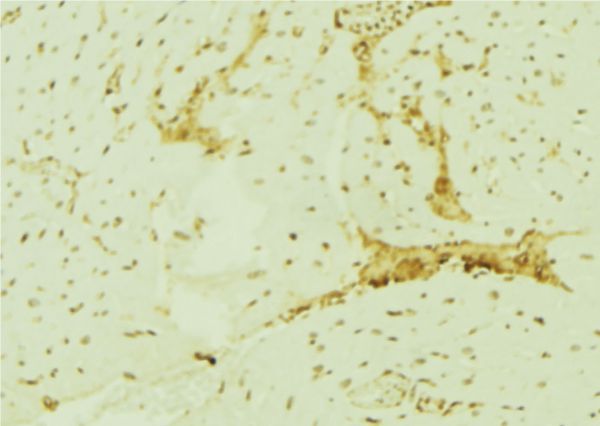

IHC (Immunohistochemistry)

(AAA326931 at 1/100 staining Human breast cancer tissue by IHC-P. The sample was formaldehyde fixed and a heat mediated antigen retrieval step in citrate buffer was performed. The sample was then blocked and incubated with the antibody for 1.5 hours at 22 degree C. An HRP conjugated goat anti-rabbit antibody was used as the secondary.)